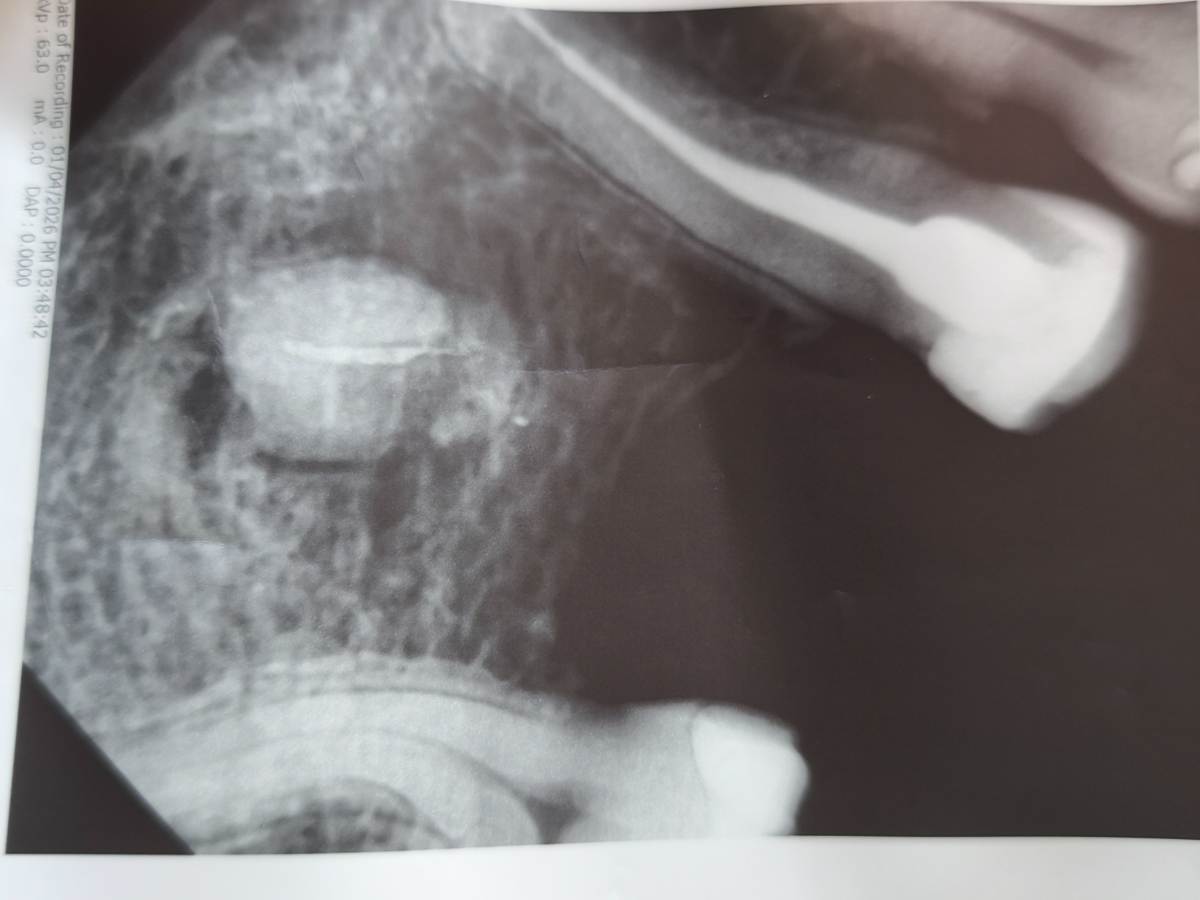

qwerty26 Опубликовано 3 часа назад Поделиться Опубликовано 3 часа назад (изменено) Добрый день. Нижняя 6 удалена давно, больше 5 лет назад . В десне, ближе к щеке появилось уплотнение, с тянущими ощущениями. На снимке это корень? Если да, то насколько сложно его удалить? Обратиться в члх надо или обратиться к хирургу достаточно? Десна зажившая полностью Изменено 3 часа назад пользователем qwerty26 Ссылка на комментарий

АнтонТЛТ Опубликовано 3 часа назад Поделиться Опубликовано 3 часа назад Добрый день, это корень. С удалением справиться любой хирург, который занимается удалением ретинированных зубов. 1 Ссылка на комментарий